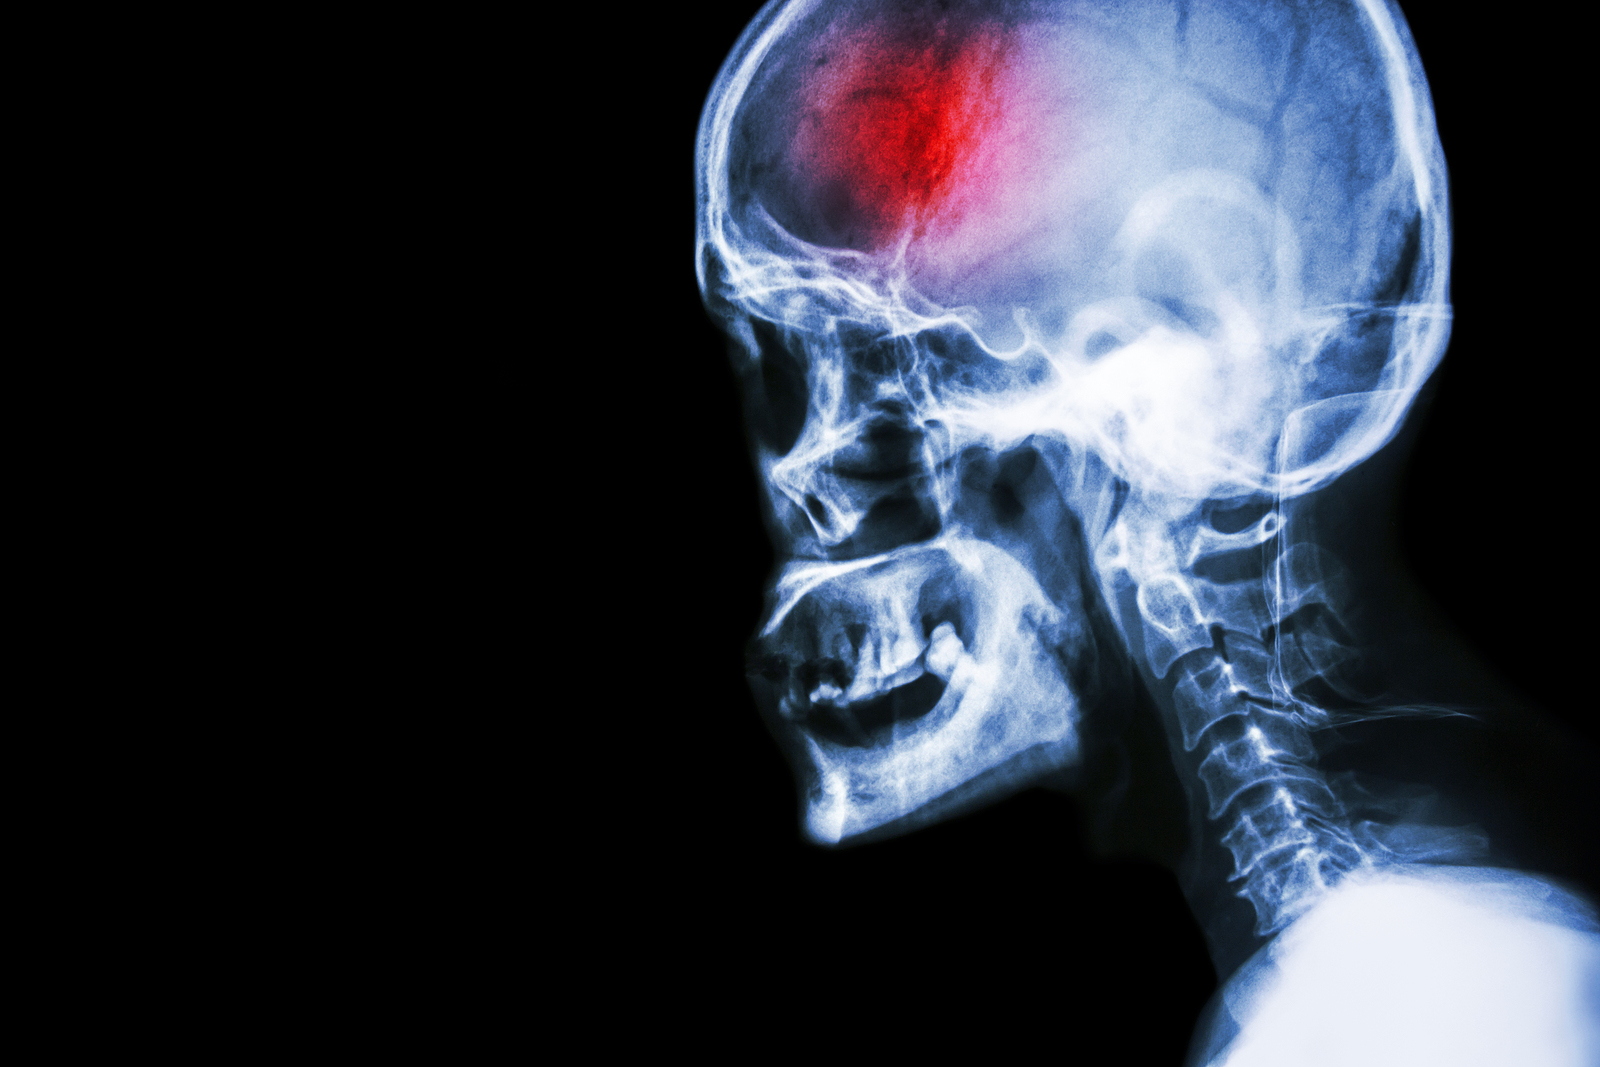

A stroke (previously known as a cerebrovascular accident) when there is a decreased flow of blood to the brain from either a blockage in the blood vessels that supply the brain (ischemic stroke), or a bleed from the blood vessels that supply the brain (hemorrhagic stroke). When the blood flow to the brain is blocked it prevents the brain from getting the needed oxygen and nutrients to function. Without oxygen the brain cells can be permanently damaged or die and the physical and mental functions related to that area of the brain will be affected. A stroke is a medical emergency and rapid treatment is crucial to decreasing the damage caused by a stroke.

- Hemorrhagic stroke: a stroke that is caused by a bleed that disturbs the blood flow to the brain and puts pressure on the surrounding tissue.